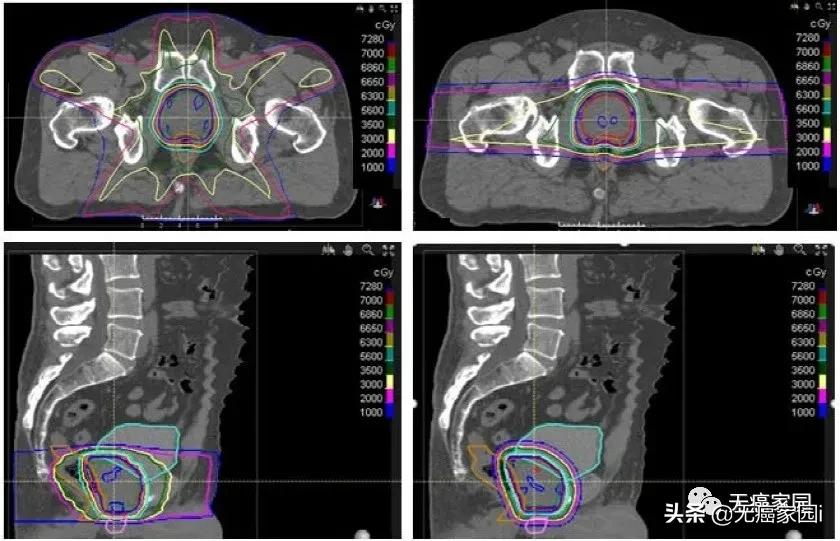

近距离放射治疗是一种治疗局限性前列腺癌的技术手段,通过三维治疗计划系统的准确定位,将放射性粒子植入前列腺内,提高前列腺的局部剂量,减少直肠和膀胱的放射剂量,其疗效肯定、创伤小。

近距离放疗尤其适合于不能耐受根治性前列腺切除术的高龄前列腺癌患者。近距离放疗联合EBRT,同时加入ADT(2或3年)是治疗高危患者的常见方案。

Chera等人对15例需要盆腔淋巴结照射的高危前列腺癌患者的IMRT和DSPT计划进行了比较。临床靶区体积(CTVs)包括盆腔淋巴结、前列腺和近端精囊。前列腺和近端精囊CTV与淋巴结CTV序贯照射,分别为46 Gy,每次2 Gy。将前列腺和近端精囊CTV推量32 Gy,总剂量78 Gy。与IMRT相比,DSPT计划显著减少了接受5~40 Gy的直肠体积,从71%减少至53%。质子治疗也显著减少了过量照射的膀胱V5~V40 GyRBE,从63%减少至40%。